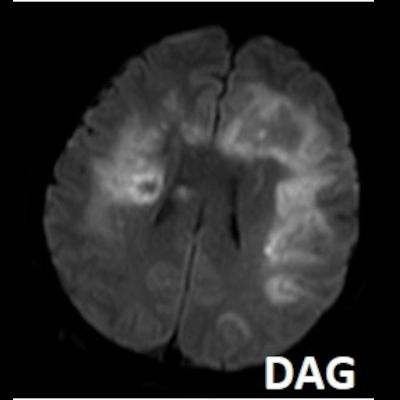

- Bilateral asimetrik subkortikal ve derin beyaz cevherde T1 ağırlıklı görüntülerde belirgin hipointens (oklar), T2A görüntülerde hiperintens (oklar), gri cevhere bakan kesimi düzgün (oklar), DAG’de hiperintens (ok) lezyonlar izlendi. Lezyonlarda T2/FLAIR uyumsuzluğu vardı (ok). Serebellar beyaz cevherde dentat nukleusu koruyan hilal işareti görüldü (ok başı). SWI sekansta sol motor kortekste hipointens kronik glioinflamatuar reaksiyon ile uyumlu sinyal değişikliği izlendi (ok başı).

- Çoğunlukla subkortikal beyaz cevherde ve U fiberlerde, asimetrik, genelde kitle etkisi yapmayan ve kontrastlanmayan demiyelinizan lezyonlar görülür. Korteks ve derin gri cevher tutulumu daha nadirdir.

- PML lezyonları, T1A görüntülerde belirgin hipointenstir. Gri cevhere bakan yüzleri keskin olup T2/FLAIR uyumsuzluğu önemli özelliğidir.